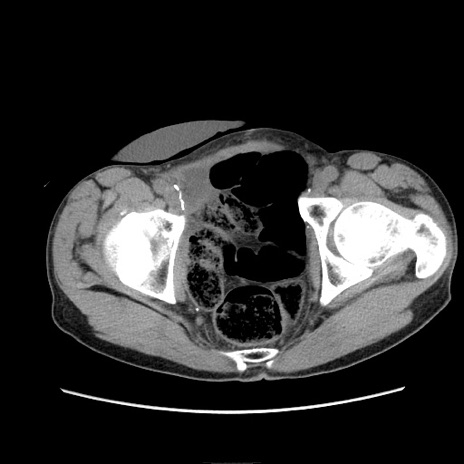

冠状断像

症例11(横断像)

【症例】 60歳代男性

【主訴】 下腹部痛

【現病歴】 本日夜中より下腹部痛の症状認め、受診。

【既往歴】 膀胱癌(膀胱全摘+尿管皮膚瘻術) 、胃癌術後

【身体所見】 BT 35.3℃、PR 58/min、BP 136/98mHg、腹部平坦、軟、腸蠕動音±、ストマ留置あり、左上腹部~正中部に圧痛あり、反跳痛なし。

【データ】WBC 5100、CRP0.01